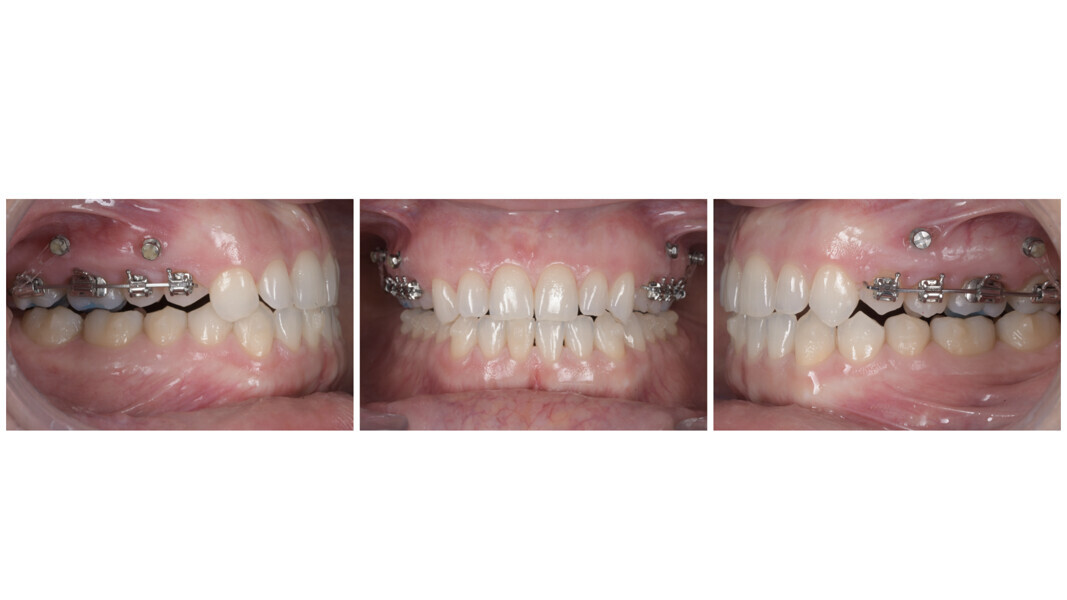

Clinical examination revealed a visible anterior open bite, a Class III dental tendency, maxillary constriction, mild crowding in both arches and a deviation of the mandibular midline to the right. The maxillary arch had a triangular shape, whereas the mandibular arch was square in form (Fig. 2).

The panoramic radiograph confirmed the presence of all four third molar germs. Notably, there was advanced root resorption in the maxillary arch, although the overall periodontal health appeared good (Fig. 3). The cephalometric analysis showed a Class II skeletal pattern, a vertical growth tendency and posterior mandibular rotation. The maxillary and mandibular incisors were found to be slightly proclined (Fig. 4).